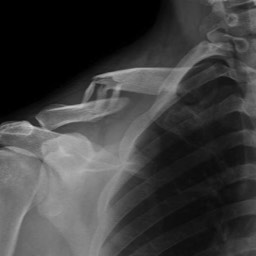

What do clavicle fractures look like on X-ray?

Below are examples of typical fractures that benefit from surgery.